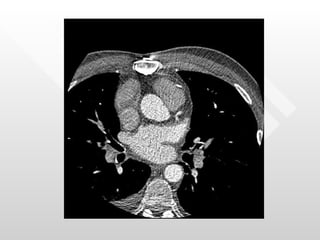

Normal pericardial thickness Multiple adhesions between the pericardium and the heart RV directly below the sternum

Normal pericardial thicknessMultiple adhesions between the pericardium and the heart RV directly below the sternum